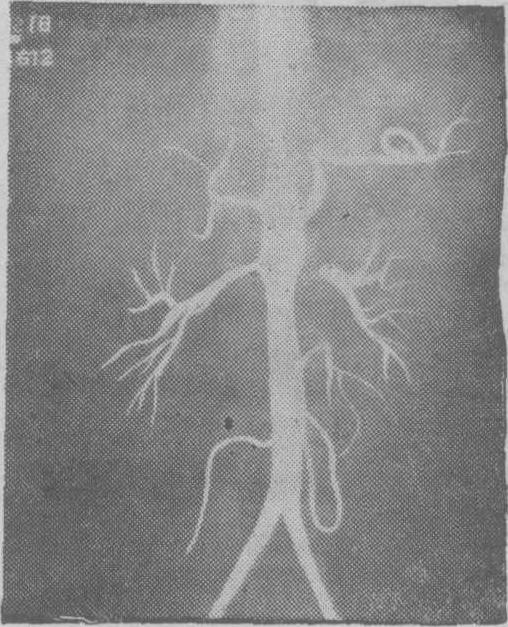

图2 腹主动脉造影

示降主动脉有狭窄,左肾动脉重度狭窄,有狭窄后扩张,右肾动脉正常。